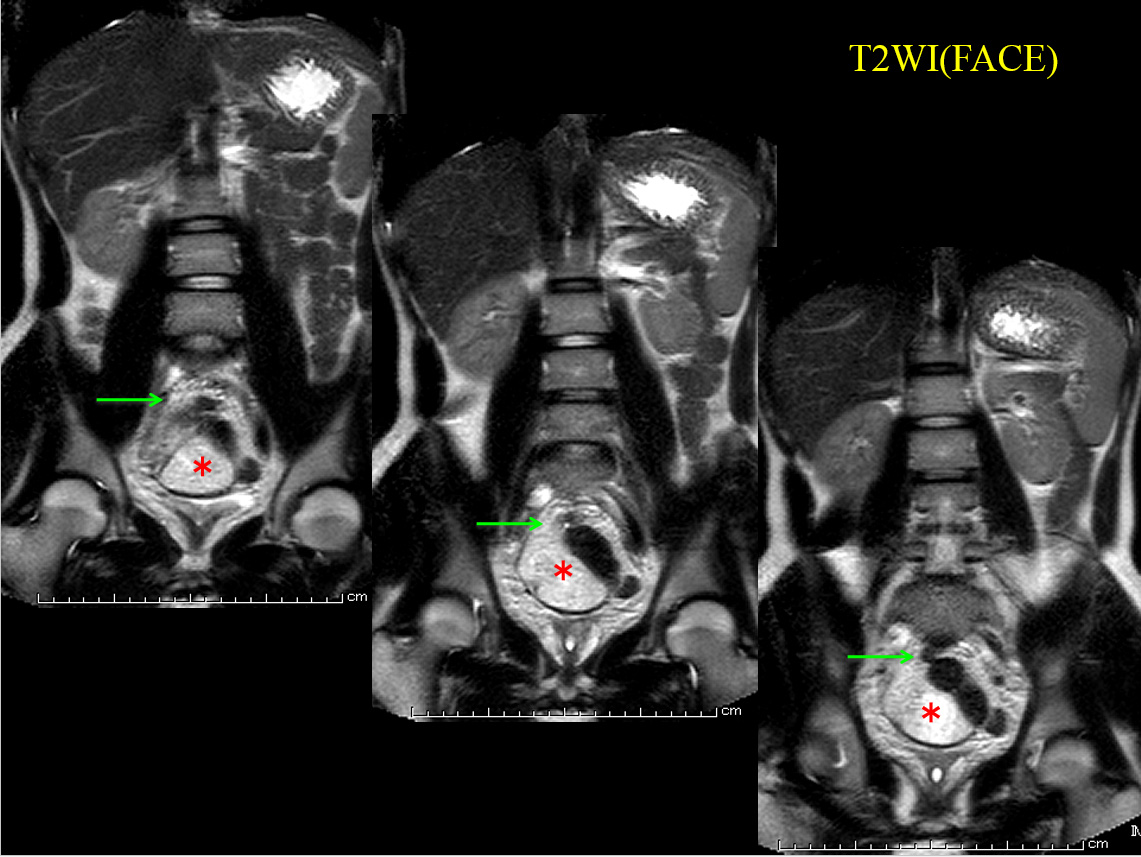

• T2WI (FACE)、

• T2WI(FACE)

MRでは、骨盤内に大きな嚢胞性病変を認める。

すなわちT2WI、T1WIでいずれも高進号を呈すが、脂肪抑制で抑制されず、造影で辺縁部のみわずかに濃染される。

内部には不均一で貯留物があると認識されるが、血性を示唆する所見には乏しい。

骨盤内の嚢胞性病変の鑑別となるが、男性であるため卵巣由来は否定的である。水平断像および冠状断像を丹念に読影すると、同病変は小腸と連続しており、腸管構造の一部であることがわかる。病変の局在は回腸末端に近く、年齢、経過を加味すると、メッケル憩室が最も考えられる。